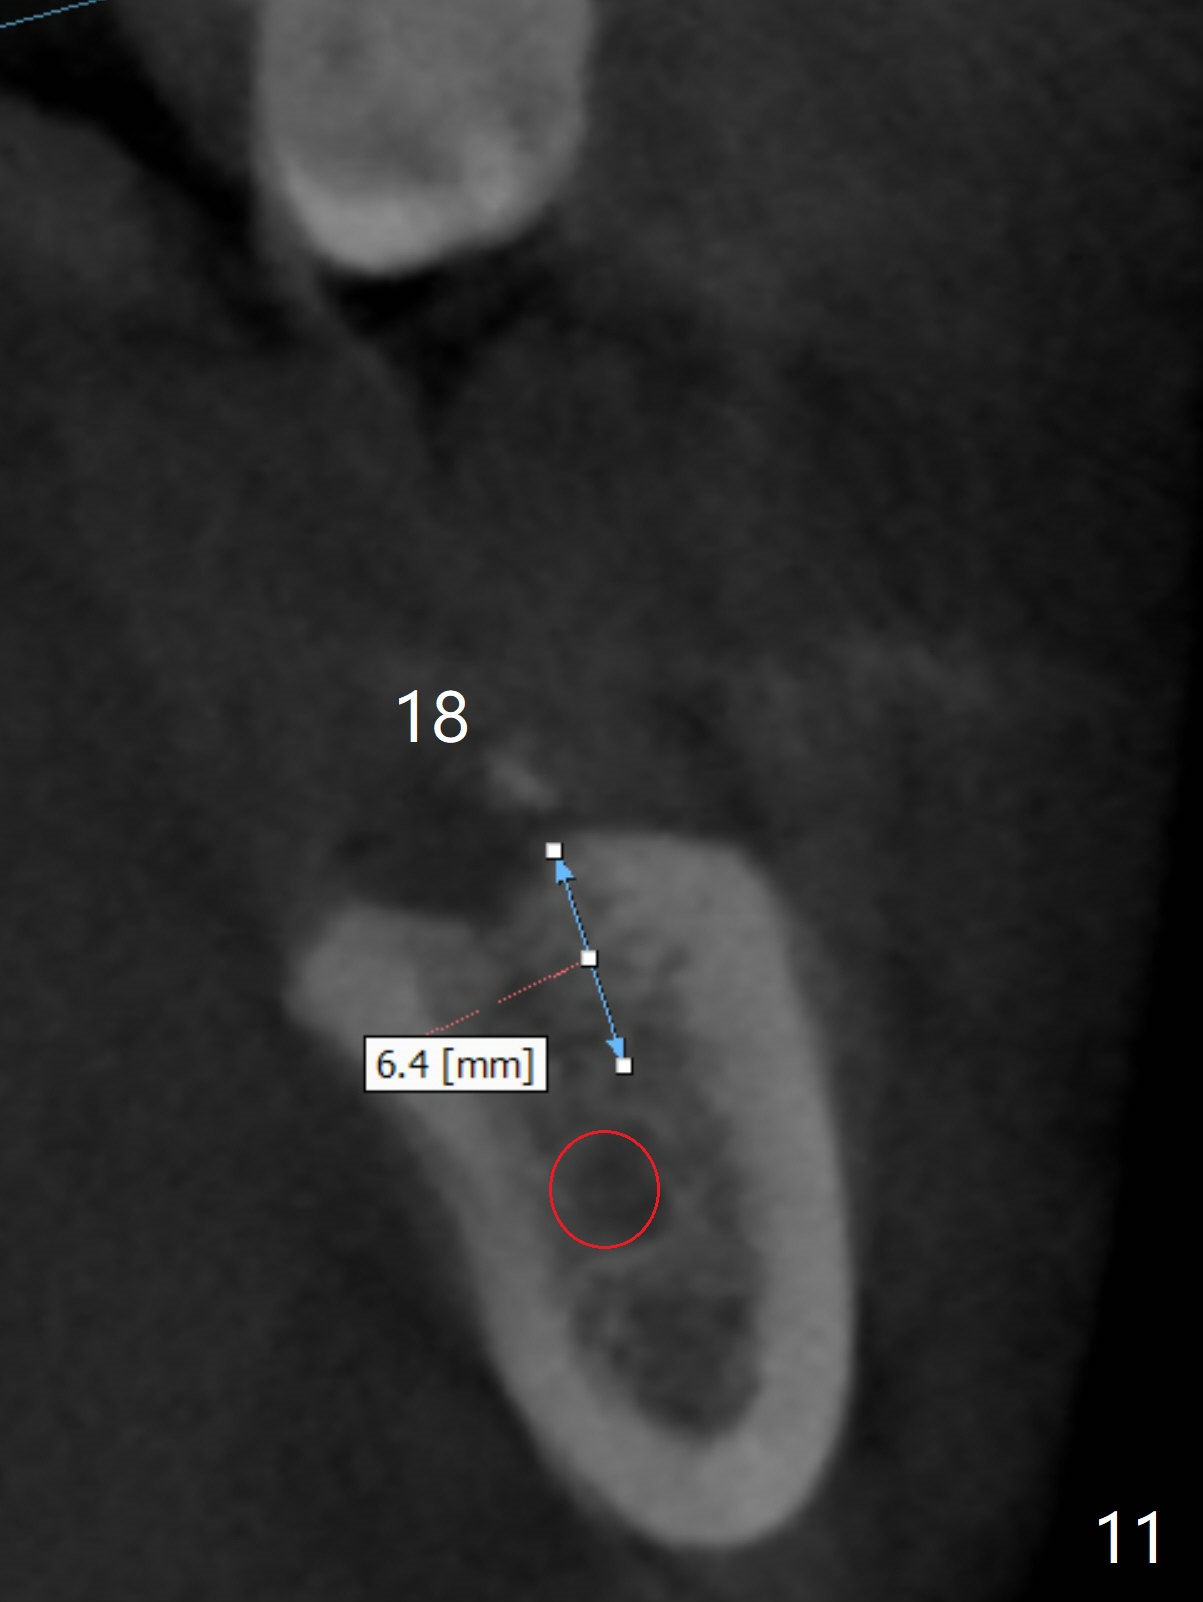

A 43-year-old man has poor dentition on the left: 1st molar missing, 2nd molar mesial inclination (Fig.1) and 2nd bicuspid lingual tilt (Fig.2). The latter is nonfunctional (Fig.3 (linguoposterior view). Two molar implants will be placed in a position so that their crowns will be in cross bite (Fig.4,5), the same occlusal scheme as the teeth #21 and 22. When these implants osteointegrate, the provisional crowns (Fig.6 P) will be supraocclusal so that there is clearance (*) for #20 to upright orthodontically (Fig.7-9). Moreover, these implants will be used anchorage as well as #21 and 22. Panoramic X-ray (Fig.1) and CBCT (Fig.10-12) show limited bone height at the sites of #18 and 19. It appears that 5x8 and 5.9x6 mm implants are appropriate with ridge reduction at #19.